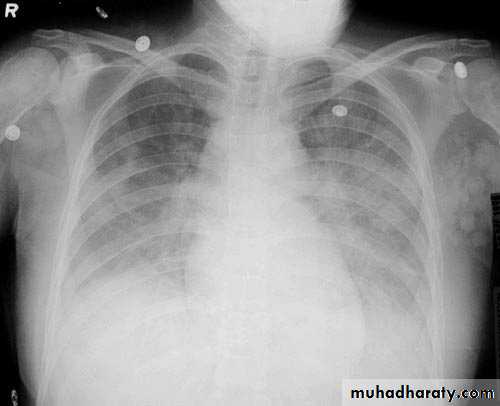

Left lower lobe collapse has distinctive features, and can be readily identified on frontal chest radiographs, provided attention is paid to the normal cardiomediastinal contours. The shadow cast by the heart does however make it harder to see than the right lower lobe collapse

Radiographic features

Left lower lobe collapseis readily identified in a well penetrated film of a patient with normal sized heart, but can be challenging in the typical patient with collapse, namely unwell patients, with portable (AP) often under-penetrated films, often with concomitant cardiomegaly. Features to be observed include :

triangular opacity in the posteromedial aspect of the left lung

edge of collapsed lung may create a 'double cardiac contour'

left hilum will be depressed

loss of the normal left hemidaphgragmatic outline

loss of the outline of the descending aorta

Non-specific signs indicating left sided atelectasis are usually also be present including:

elevation of the hemidiaphragm

crowding of the left sided ribs

shift of the mediastinum to the left